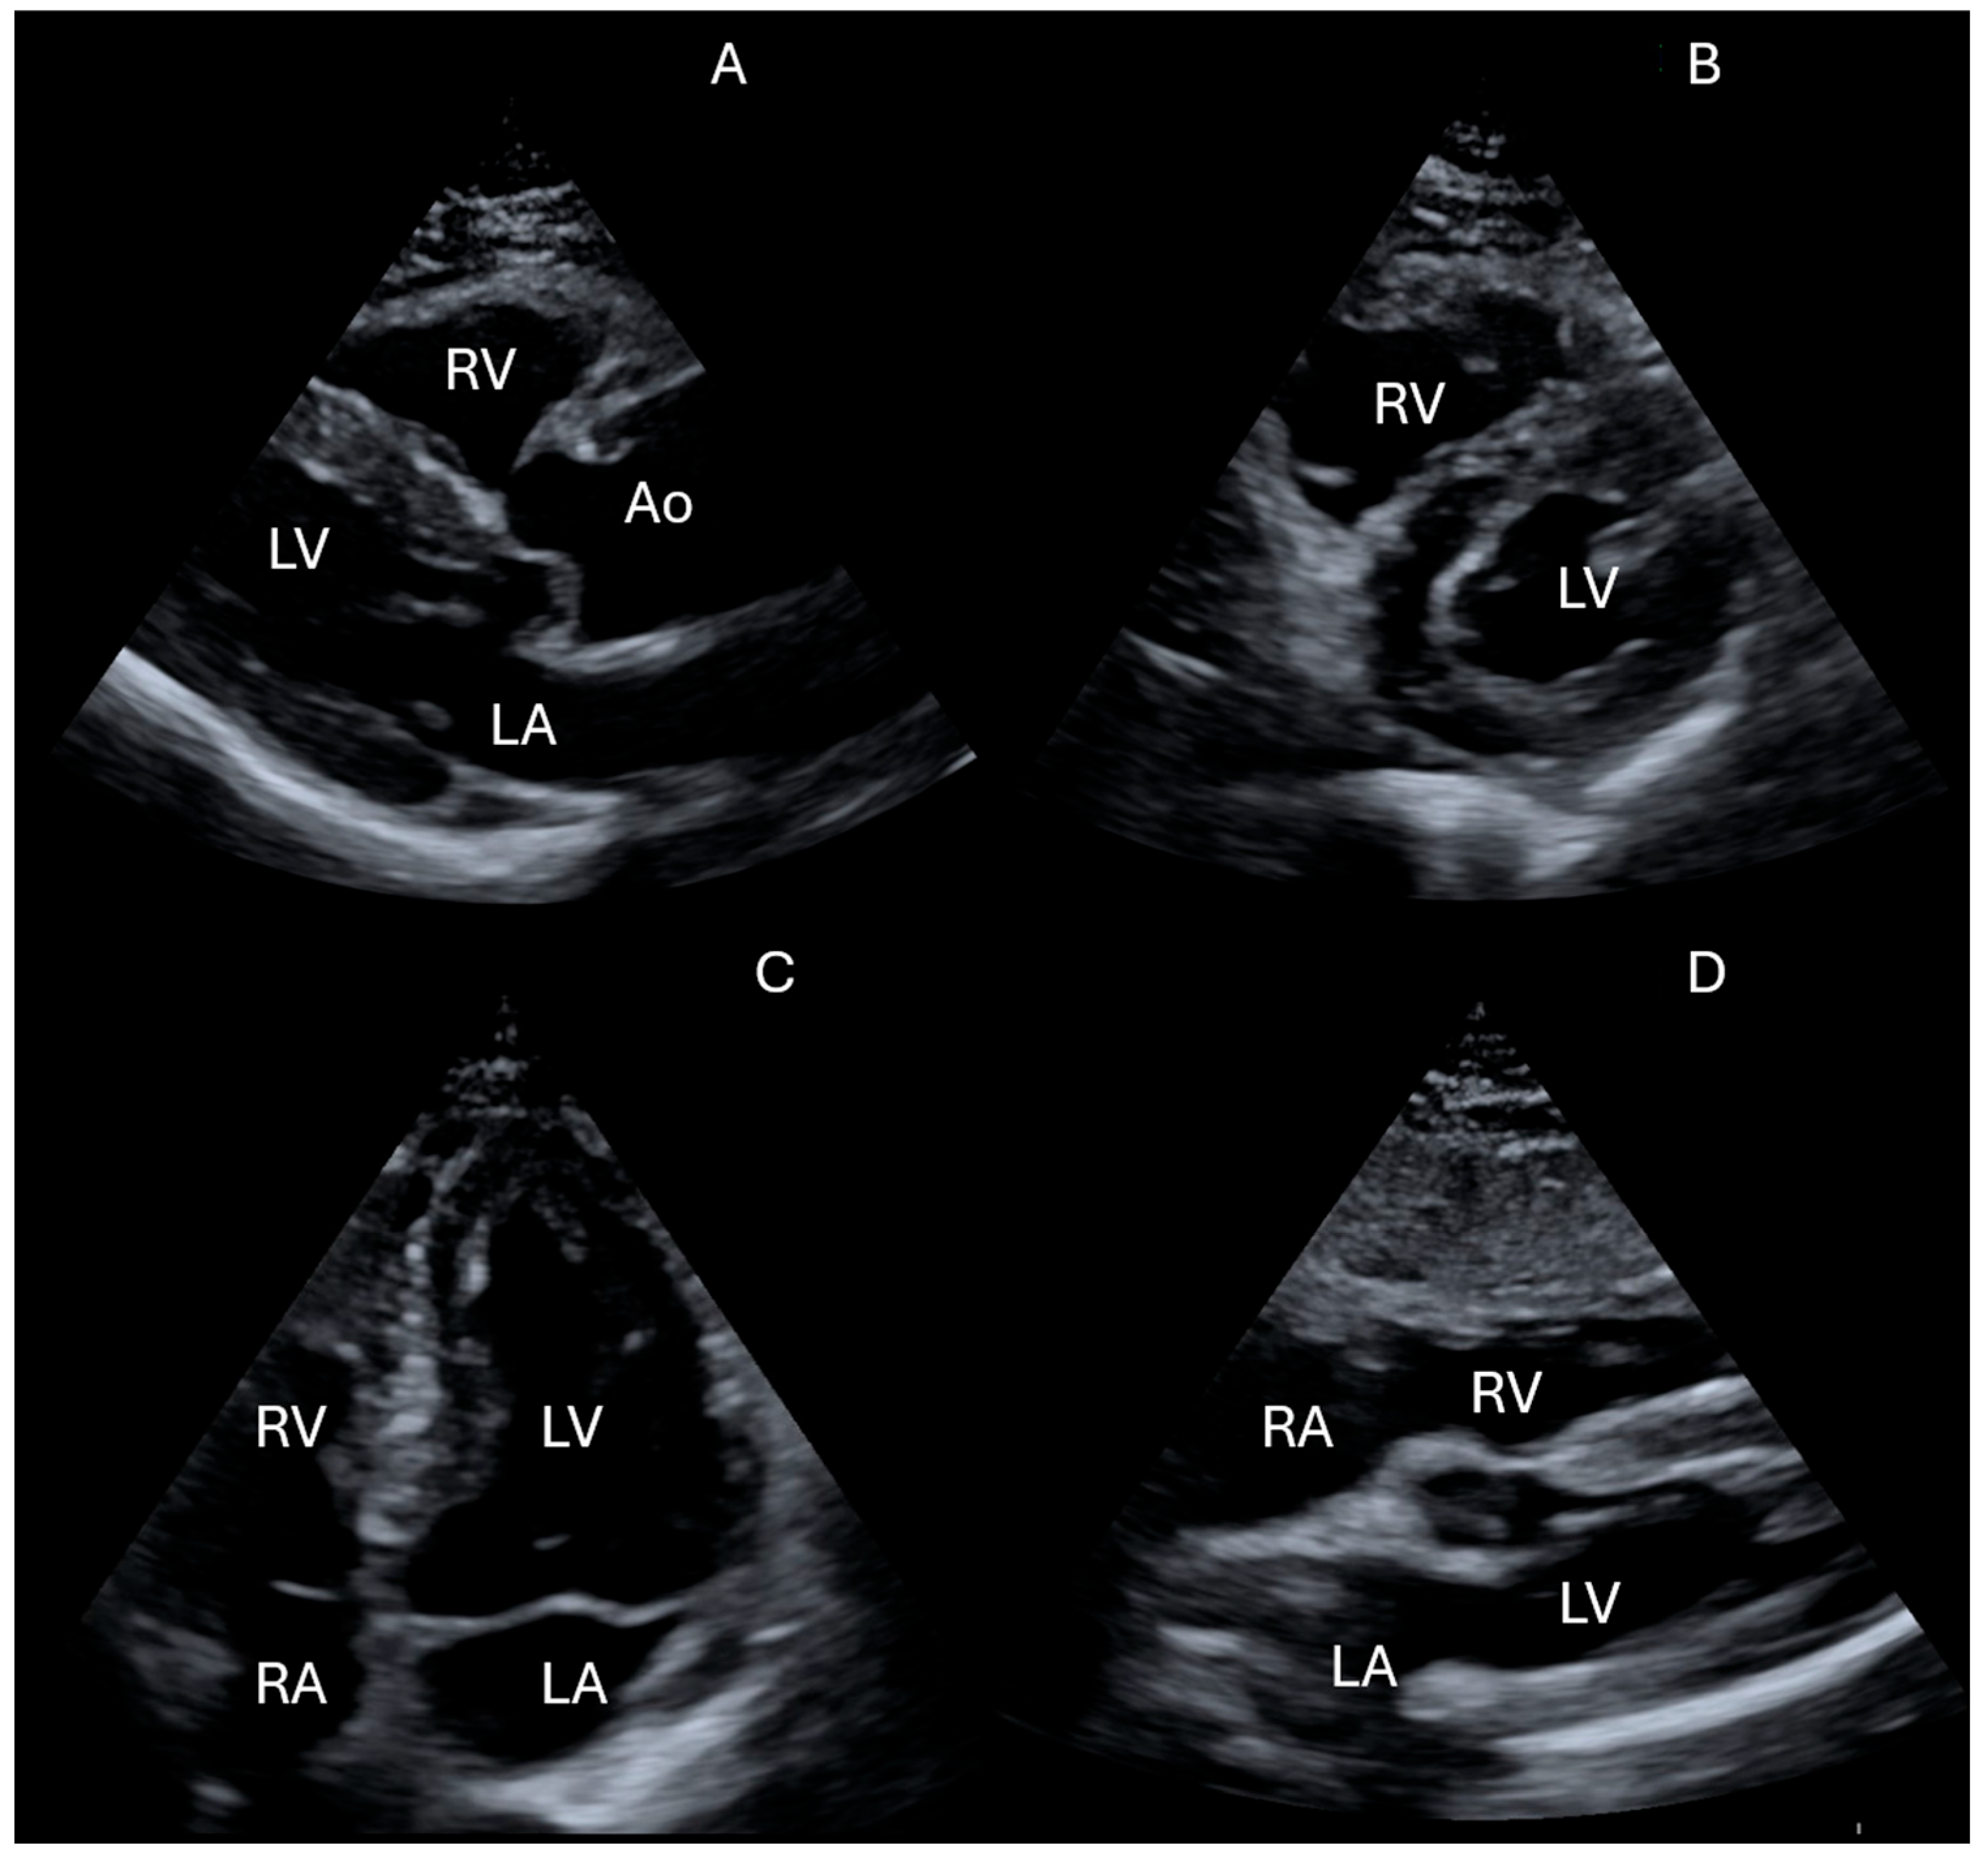

- Is there left ventricular systolic dysfunction?

- Is the IVC dilated or collapsible?

- Is there pericardial effusion or tamponade?

- Are there signs of the right ventricular strain?

- Neskovic, A.N.; Skinner, H.; Price, S.; Via, G.; De Hert, S.; Stankovic, I.; Galderisi, M.; Donal, E.; Muraru, D.; Sloth, E.; et al. Reviewers: This document was reviewed by members of the 2016–2018 EACVI Scientific Documents Committee. Focus cardiac ultrasound core curriculum and core syllabus of the European Association of Cardiovascular Imaging. Eur. Heart J. Cardiovasc. Imaging 2018, 19, 475–481. [Google Scholar] [CrossRef]

- Neskovic, A.N.; Edvardsen, T.; Galderisi, M.; Garbi, M.; Gullace, G.; Jurcut, R.; Dalen, H.; Hagendorff, A.; Lancellotti, P.; European Association of Cardiovascular Imaging Document Reviewers; et al. Focus cardiac ultrasound: The European Association of Cardiovascular Imaging viewpoint. Eur. Heart J. Cardiovasc. Imaging 2014, 15, 956–960. [Google Scholar] [CrossRef]

| Parameter/Measurement | Basic Cardiac FoCUS/PoCUS | Advanced FoCUS | Comprehensive Echocardiography (TTE) |

| LV systolic function (visual) | Yes (qualitative only) | Yes (semi-quantitative; visual + basic metrics) | Yes (quantitative, biplane Simpson/3D) |

| Regional wall-motion abnormalities | Limited (gross only) | Yes (screening) | Yes (standard) |

| RV size (base/mid/RA) | Yes (screening) | Yes (with basic metrics) | Yes (standard) |

| IVC diameter & collapsibility | Yes | Yes (with trending) | Yes (plus RA pressure estimate) |

| Pericardial effusion—detection | Yes | Yes | Yes |